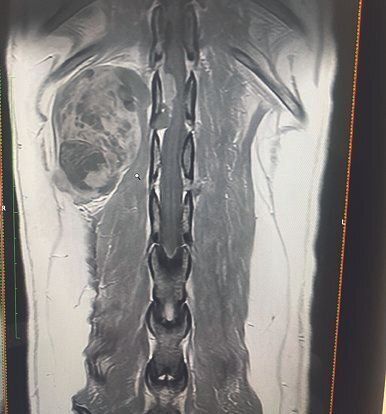

手術前のMRI画像。脊椎の左側に大きな腫瘍があり、脊髄内への浸潤も写っています

「ポッキーの腫瘍は末梢神経にも広がっているのですべて取りきるのは難しく、転移の可能性もあるので手術をしても再び歩ける保証はないとの説明を受けました。でも、ほんの少しでもチャンスがあるのなら、それに賭けたかった」とBさんは話します。